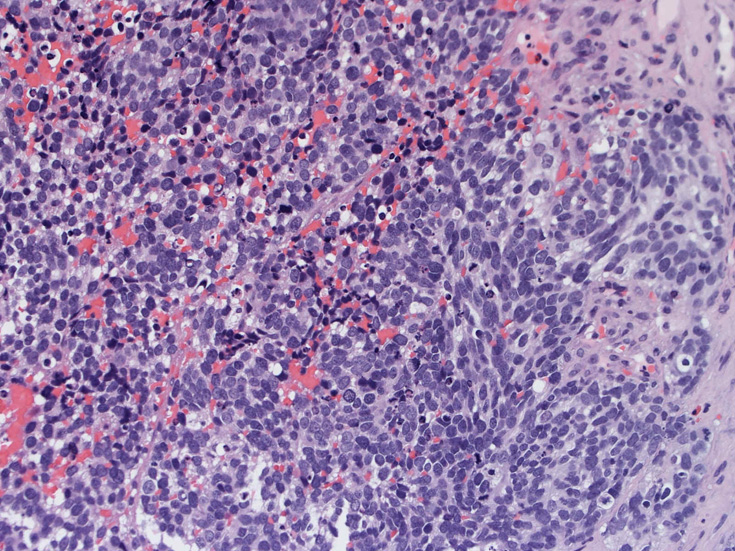

30歳代男性 鼻腔腫瘤の生検組織

厳密にはalveolar patternが明らかではなく, solid typeに入る症例かもしれない。異型細胞増殖胞巣が線維化組織に取り囲まれるように散在している. 小さな生検組織のため全体像が不明である。